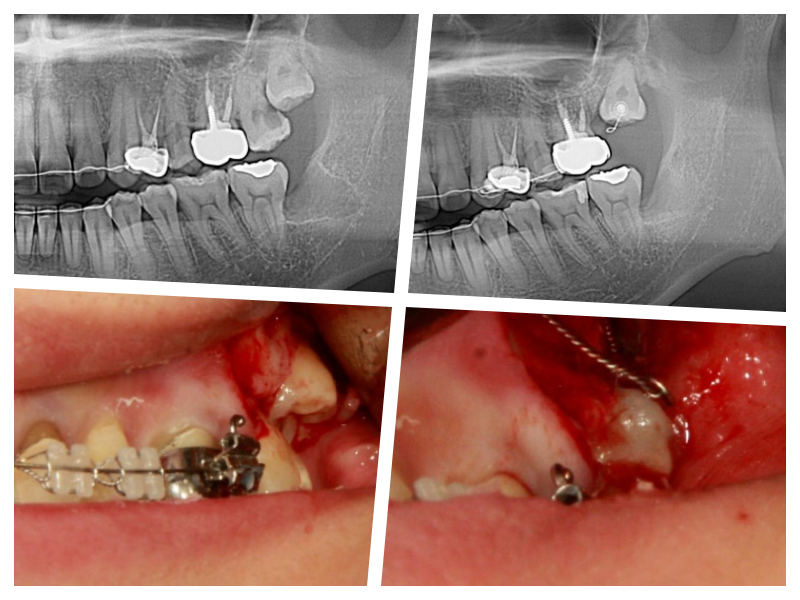

사랑니의 쓸모를 찾아서~

사랑니 교정

사랑니를 교정치료를 통해 어금니로 사용하는 케이스